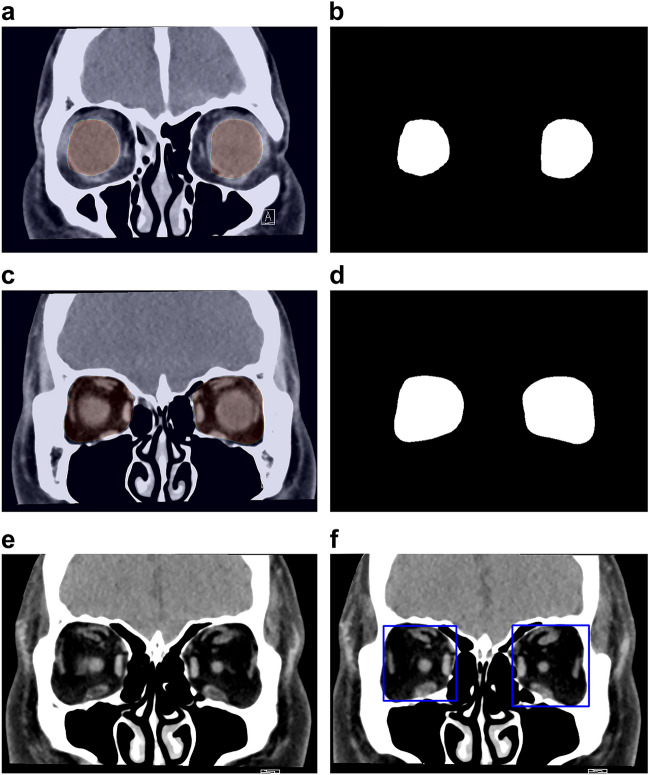

The DL model and its training

The DL algorithm consists of four main processes: (1) extraction of the retrobulbar region from the CT image; (2) trimming of the orbital area on the CT image; (3) classification of the presence or absence of hypertrophied extraocular muscle; and (4) evaluation of extraocular muscle abnormality in GO. For down-sampling and up-sampling, the neural network architecture for segmentation was obtained through Residual Network-5025 (Supplementary Fig. S1). First, the globe was segmented on coronal CT slices, and the orbital region posterior to the segmented globe was segmented and trimmed using Residual Network-50 (Fig. 4). The code is provided in the supplemental data. Next, all rectus muscles judged by the neuro-ophthalmologist to be abnormal on coronal CT were tagged. For classification, we used the Visual Geometry Group-1626 as the neural network and trained the DL system using the tag (Supplementary Fig. S2). The neural network generates the probability for each slice’s category (e.g., 0.1 for normal and 0.9 for abnormal). If the probability of “abnormal” exceeds a certain threshold, the slice is considered abnormal. We calculated this threshold from the validation data. Additionally, we calculated the proportion of slices considered abnormal by the neural network. If the proportion exceeded a certain threshold, the CT data as a whole was judged to reveal extraocular muscle abnormalities.

Figure 4.

The coronal slice (a) and the result (b) used for the segmentation of the eyeball. The coronal slice (c) and the result (d) were used for the orbit segmentation. The coronal slice (e) and region of interest (the area inside the blue squares) (f) used when Residual Network-50 recognized the retrobulbar region from (b) and (d).